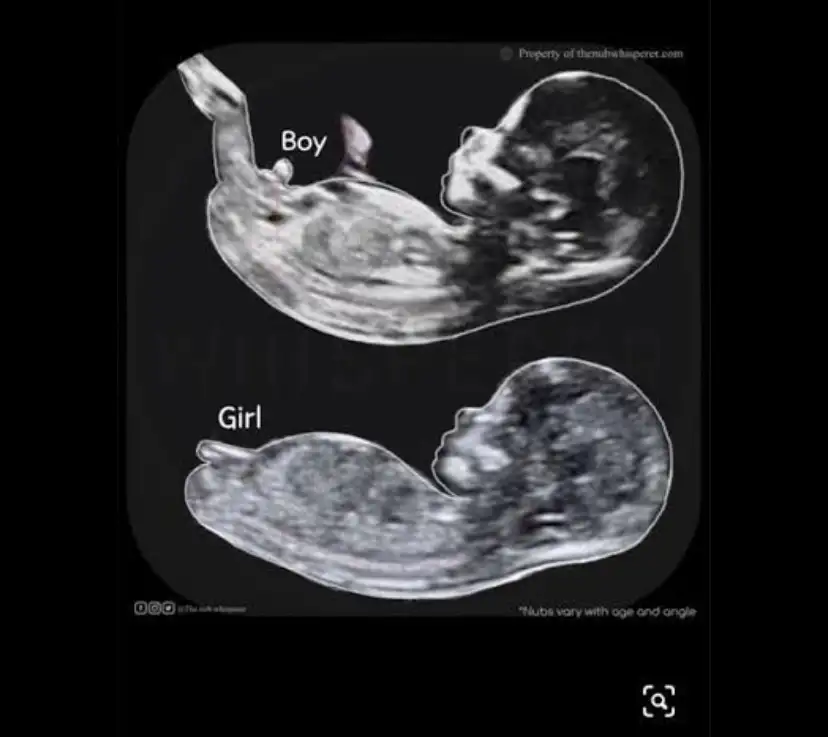

kafamda bir nub teorisi resmi var netten bulmuştum onu. ona benzetmeye çalışıyorum

ben mesela seninkini o resme göre yorumladığımda kız görüyorum ama doktorun erkek gibi demiş yani ben de çok anlamıyorum demek ki